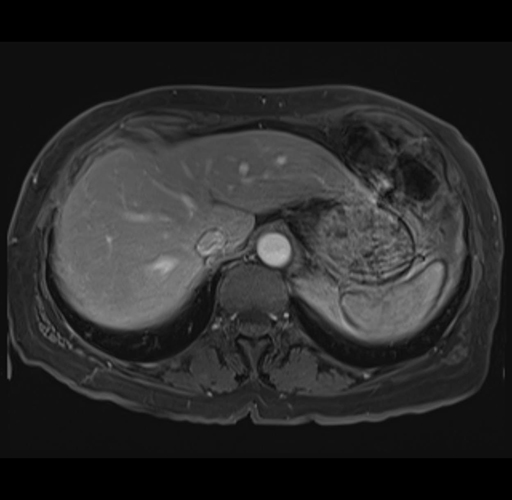

MRI T1

Imaging analysis

Based on your CT findings, which issue(s) would give reason for "planned slowing down moment(s)" in this case?

Considering a standard right hepatectomy procedure, what step(s) of the operation would you do differently in this case?